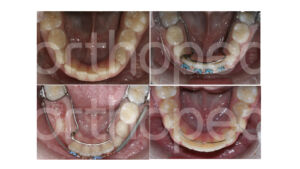

Bom, esses são os casos em que me preocupo com a obtenção de espaço ainda na dentição mista. De maneira geral há 4 formas de obtenção de espaço: projeção de incisivos, expansão do arco, distalização de dentes e redução do volume dentário (desgaste ou exodontia). Quando falamos de um paciente em dentição mista, a redução do volume dentário ou exodontia será conduzida em um número muito pequeno de casos, diria até que menos de 1% dos casos. Essas situações clínicas normalmente são aquelas em que houve perda precoce de dentes decíduos e mesialização importante do primeiro molar permanente. Portanto, nos resta aqui 3 opções clínicas: projeção de incisivos, expansão do arco e distalização de dentes. A distalização de dentes nessa fase é um procedimento crítico, pois na fase de dentição mista ainda não temos a presença do segundo molar permanente e a distalização do primeiro molar pode implicar em impacção do segundo. O que podemos considerar nessa fase é a verticalização do primeiro molar como forma de obter até 2,5mm de espaço no arco. Para tal, costumamos usar uma placa lábio-ativa (P.L.A.). Esse tipo de dispositivo contribui para essa verticalização do primeiro molar permanente.

Além da projeção de incisivos e verticalização molar, a outra alternativa para obtenção de espaço no arco pode ser a expansão do arco. Apesar do arco inferior não apresentar sutura e portanto, apresenta limitação na expansão do arco, essa pode ser uma boa alternativa de tratamento. A expansão dentoalveolar do arco inferior consiste na verticalização dos dentes.

De acordo com McNamara, o uso de um dispositivo expansor removível no arco inferior pode resultar em obtenção de até 3,8 mm de espaço no arco quando associado à expansão rápida da maxila.

Gosto bastante de associar a expansão inferior com a expansão rápida da maxila. A verticalização dos dentes posteriores otimiza os efeitos da expansão superior e permite melhor relação entre os arcos.